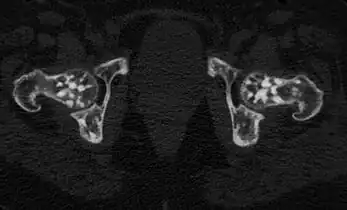

In terms of the diagnosis Osteopoikilosis is radiographically evaluated via the presence of multiple symmetrical circular sclerotic opacities [2]

The radiographic appearance of osteopoikilosis on an X-ray is characterized by a pattern of numerous white densities of similar size spread throughout all the bones. This is a systemic condition. It must be differentiated from blastic metastasis, which can also present radiographically as white densities interspersed throughout bone. Blastic metastasis tends to present with larger and more irregular densities in less of a uniform pattern. Another differentiating factor is age, with blastic metastasis mostly affecting older people, and osteopoikilosis being found in people 20 years of age and younger.

The distribution is variable, though it does not tend to affect the ribs, spine, or skull.[3]

Osteopoikilosis of the hips on CT. -